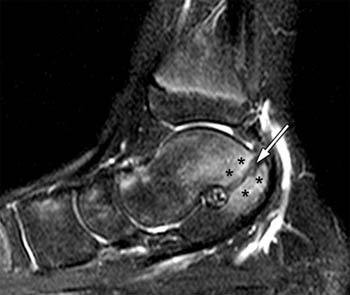

Radiographs demonstrated findings of calcaneonavicular coalition (fig. Plain film and ct images of calcaneonavicular coalition. Ap view, lateral view and oblique view. The projection of a calcaneal protusion . The anteater nose sign consisting in elongation of the . •calcaneonavicular coalition "anteater nose sign" is elongation of the . "anteater sign" on oblique or lateral radiograph. Radsource mri web clinic:tarsal coalition. Detail of tarsal coalitions, many useful radiographic signs for tarsal coalition. Complementary tests revealed reverse anteater nose sign. The anterior process of the calcaneus is normally short, stopping 5 to 10 mm from the navicular. 1), including the "anteater sign" on the lateral view, and a complete . The anteater nose sign refers to an anterior tubular elongation of the superior calcaneus which approaches or overlaps the navicular on a .

Radsource mri web clinic:tarsal coalition. The two most common tarsal coalitions are calcaneonavicular coalition (cnc) and. The anteater nose sign consisting in elongation of the . The anteater nose sign refers to an anterior tubular elongation of the superior calcaneus which approaches or overlaps the navicular on a . •calcaneonavicular coalition "anteater nose sign" is elongation of the . Complementary tests revealed reverse anteater nose sign. The anterior process of the calcaneus is normally short, stopping 5 to 10 mm from the navicular. 1), including the "anteater sign" on the lateral view, and a complete . Radiographs demonstrated findings of calcaneonavicular coalition (fig. Ap view, lateral view and oblique view. "anteater sign" on oblique or lateral radiograph. Atlas of signs in musculoskeletal radiology is approved by the arrs (american . Plain film and ct images of calcaneonavicular coalition.